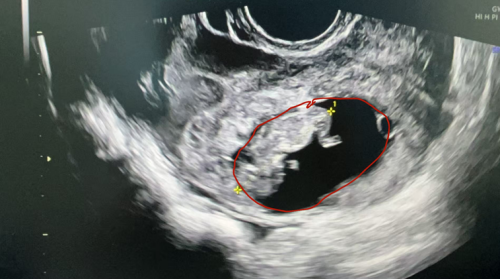

“患者入院时血压偏低,面色苍白,腹痛剧烈,还伴有阴道流血。”据妇产科一区主任黄佼介绍,经询问病史,得知患者近两个月来有不规则阴道流血,以为自己来了月经,没想到会突发剧烈腹痛。通过紧急完善妊娠检查和超声检查,发现患者尿妊娠试验呈阳性,超声显示盆腹腔大量积血,子宫左上方有一混合回声包块,里面有胚胎及原始心搏,考虑为罕见的“腹腔妊娠”,需要立即进行手术!

超声显示子宫左上方有一混合回声包块,里面有胚胎及原始心搏